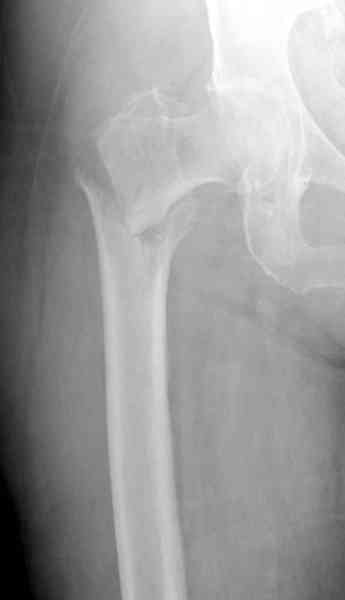

В общем, сделали. См. приложение.

Длина и из-за этого ось получились не совсем такие, как хотелось бы, все-таки срок после той операции уже 6 недель. Может быть, стоило провести дистракцию аппаратом неделю-другую. Заранее спасибо за комментарии и критику.

Очевидно была неправильно, причем, очень неправильно! точка введения штифта.

Наверное так и надо сделать. Будет непросто предотвратить при введении смещение Гаммы кнаружи через имеющийся дефект кортикала. Уверен, Александр Николоевич, Вы с эти справитесь. Удачи!